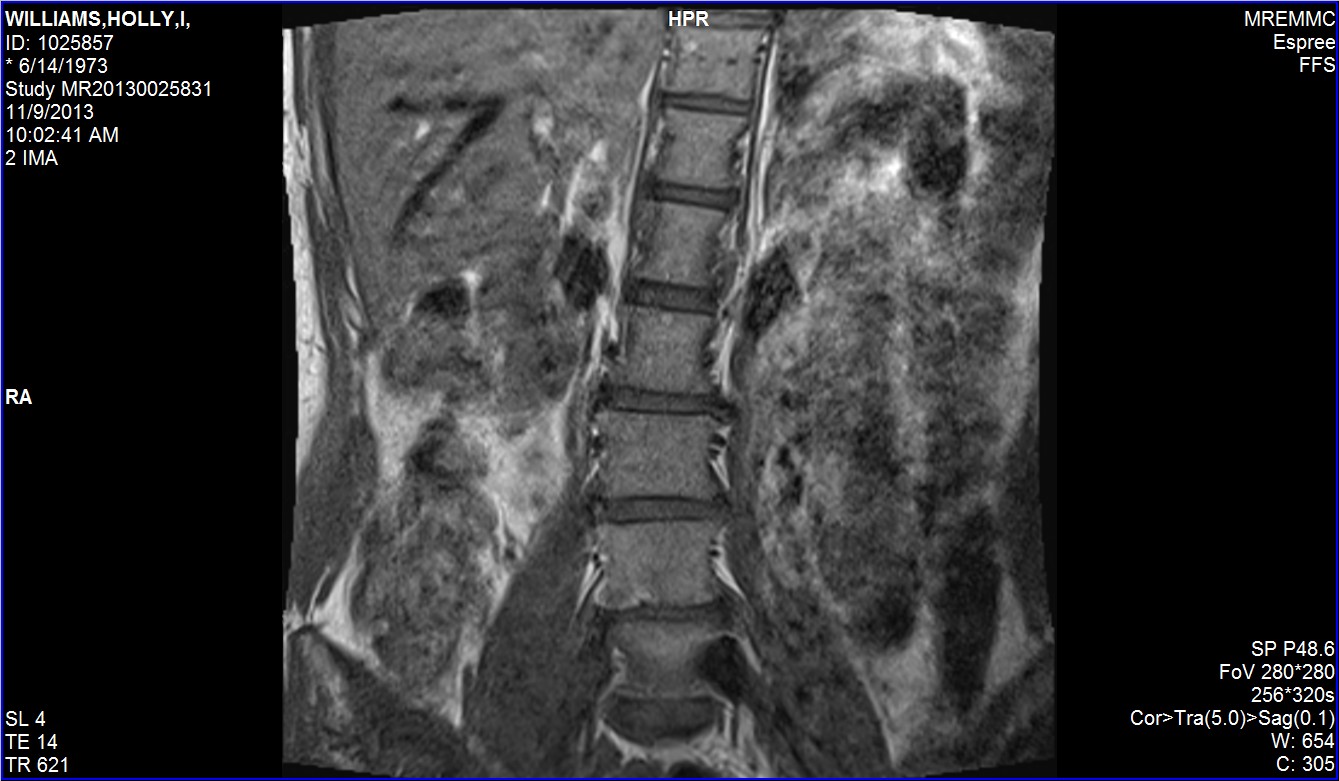

I wish I could tell you more about what this MRI says, but I have no idea. This was taken just this morning, so I’ll talk to my doc next week. There are several things I found interesting, though, even if I don’t know what they mean. I apparently have the number 7 inside of my body (upper left hand side). That is officially my lucky number now. 🙂 And my spine looks awfully crooked. I’m hoping that is how I was lying down, but I don’t know. And lastly, I love that I can see the hourglass figure of my body in this. See my indented waist? Isn’t that freakin’ adorable?!?